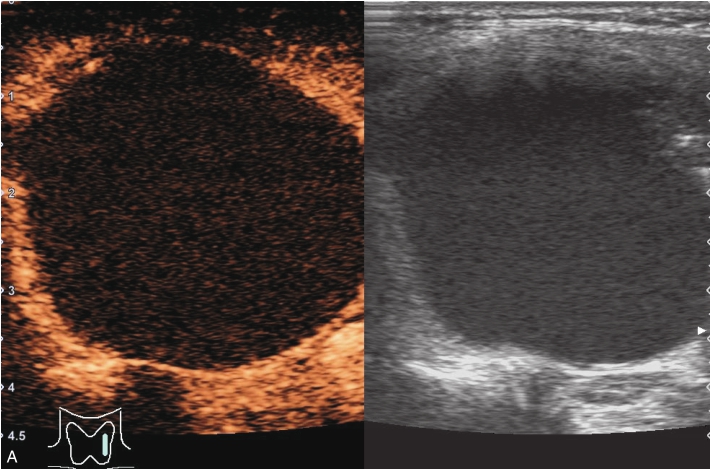

甲状腺左叶明显增大,可见一囊性为主的囊实性结节,该结节体积较2年前明显增大,挤压周围甲状腺组织,结节内部回声欠均匀,见多发点、条状强回声,结节后方回声增强;CDFI显示结节内部未见明显血流信号,见图1-3-3。

图1-3-3 甲状腺囊肿伴出血常规超声声像图

A.甲状腺左叶横切面;B.CDFI血流图

注入造影剂后甲状腺左叶囊实性结节内始终呈无增强,边界清晰,结节周围甲状腺被膜完整,见图1-3-4、ER1-3-2。

(1)周围囊壁呈均匀高增强,边界清,内部始终无造影剂灌注。

(2)结节周边被膜连续且完整。